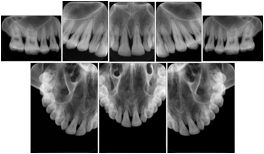

In most standard cases, images are oriented in structured layouts. These structured displays are useful to be shared between providers for reference purposes.

Table OO.1.1-1 shows structured display standard templates, where Viewset ID is based on the Japanese Society for Oral and Maxillofacial Radiology (JSOMR) classification provided by JIRA (Japan Medical Imaging and Radiological Systems Industries Association, www.jira-net.or.jp). Expected or typical teeth to be imaged location, region and designation codes are based on ISO 3950-2010, Dentistry - Designation system for teeth and areas of the oral cavity. For all the hanging protocols listed in OO.1.1-1, the value to use for Hanging Protocol Creator (0072,0008) is "JSOMR" and the value to use for Hanging Protocol Name (0072,0002) does not include "JSOMR" (e.g., "DL-S001A", not "JSOMR DL-S001A").

Table OO.1.1-1. Hanging Protocol Names for Dental Image Layout based on JSOMR classification